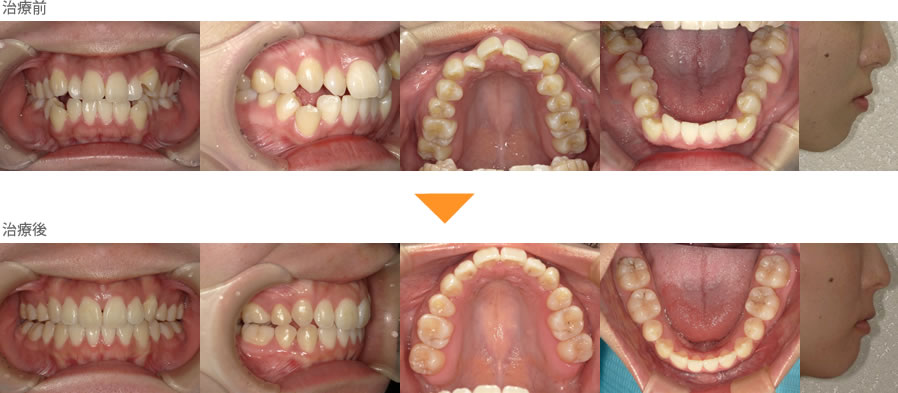

(症例2)上下の前歯が出ている。下の歯がガタガタしている。

- 年齢

- 20代

- 性別

- 男性

- 期間

- 約1年6ヶ月

- 費用

- 約80万円(治療時)

- リスク清掃不良による虫歯、痛みを伴うことがあります。

上下の歯が前にでています。歯が前に傾いていますので、口元が少し出ているように見えます。

矯正後の歯並びでは、歯の傾きが改善されており、口元の突出感も改善できました。

インビザライン(マウスピース)で部分矯正をしますと、目立ちにくく、治療できます。